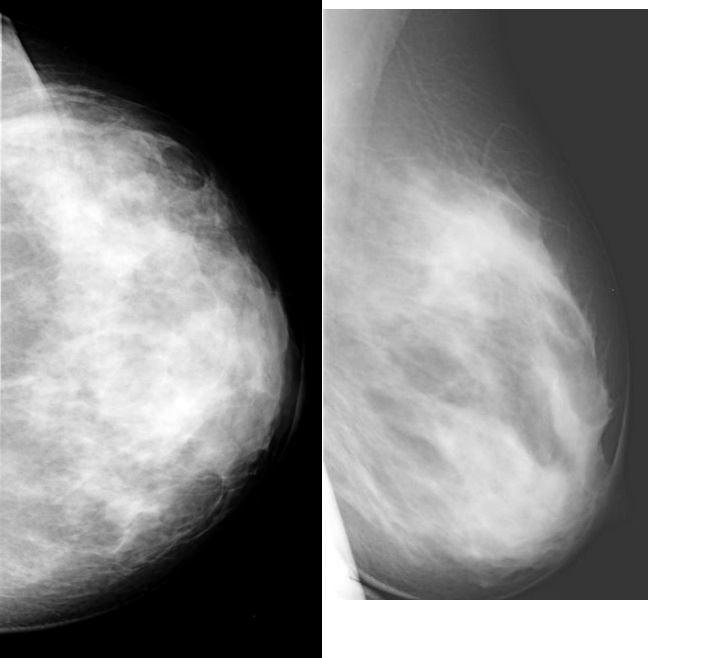

Что такое маммография: важность, процесс и результаты

Раздел: Необычные решения